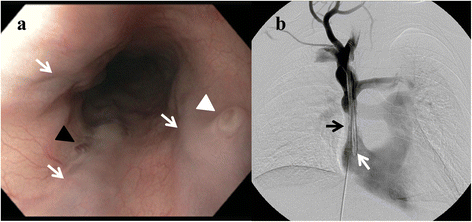

Le diagnostic se fait par endoscopie digestive haute, on retrouve un aspect de cordons bleuâtres, saillants, au niveau de la partie inférieure de l’œsophage.

Le traitement local consiste, par voie endoscopique, à parvenir à l'occlusion des varices, soit par injection d'un liquide sclérosant, soit par ligature de leur origine. La seconde technique semble être supérieure à la première en termes de résultats sur l'évolution de la maladie. Dans les deux cas, le risque de récidive existe, imposant une surveillance par fibroscopie répétées.

Le traitement de la rupture est une urgence médico-chirurgicale. Il consiste à la stabilisation de l’état hémodynamique du patient par transfusion sanguine, et par la diminution de la pression portale par différents médicaments (dont la Terlipressine). Le traitement local repose sur la réalisation rapide d'une endoscopie pour ligature ou sclérose de la varice responsable.

La constitution d'un shunt porto-cave par voie veineuse (veine jugulaire interne), appelé aussi TIPS ou TiPSS pour l'anglais : Transjugular intrahepatic portosystemic shunt, peut être une option intéressante dans certains cas.